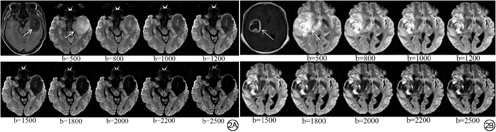

采用GE Signa Architect 3.0 T MRI系统对sDWI数据进行测量和分析。由2名分别在神经影像诊断方面具有3年及5年诊断经验的住院医师及主治医师分析图像,且对患者病理结果、临床资料和其他影像学检查结果不知情。分析步骤:(1)选择MUSE-DWI序列,进入主机系统sDWI界面,由已扫描的MUSE-DWI序列(b值为0和1000 s/mm2)通过后续计算合成b值范围为0~2500 s/mm2的DWI图像即sDWI;(2)结合T2 FLAIR及增强T1WI(T1WI+C)图像避开病灶出血、坏死、囊变区,选取相对容易识别的DWI高信号区域画取ROI测量病灶的信号强度(ROI范围为0.3~0.5 cm2);(3)根据以上原则选择特定b值三处不同ROI测量病灶的信号强度(图1),取其平均值。2周后2名观察者再次用同样的方法对这些数据进行重复测量。

sDWI不同b值高低级别胶质瘤信号强度比较显示:b值分别为500、800、1000、1200、1500、1800、2000、2200、2500 s/mm2时对应的信号强度在高低级别胶质瘤组间差异均具有统计学意义(P<0.001)(表1)。二元Logisitic回归分析显示b=2500 s/mm2的DWI图像对应的信号强度是预测高低级别胶质瘤的独立变量。ROC曲线分析显示b值为2500 s/mm2时诊断准确率最高,AUC为0.935,相应的敏感度为98%、特异度为87%。其余b值为2200、2000、1800、1500、1200、1000、800、500 s/mm2时AUC分别为0.929、0.925、0.919、0.915、0.909、0.905、0.859、0.757(表2)。sDWI图像随着b值升高,病灶与周围组织对比度越高,清晰显示瘤体周围囊变、坏死(图2)。